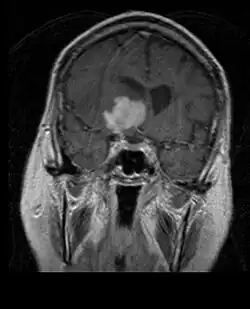

Durch Computertomographie (CT) und Kernspinresonanztomographie (MRT) kann eine Neoplasie im Gehirn effektiv nachgewiesen werden. Zur Identifizierung von Läsionen ist die MRT empfindlicher als die CT, weist aber für Patienten mit Herzschrittmachern, inkompatiblen Prothesen, Metallklammern und anderem Kontraindikationen auf. Die CT bleibt die Methode der Wahl, um Verkalkungen innerhalb der Läsionen oder Knochenerosionen der Schädeldecke oder -basis zu erkennen. Die Verwendung von Kontrastmitteln, die im Fall der CT jodiert und im Fall der MRT paramagnetisch (Gadolinium) sind, ermöglicht die Erfassung von Informationen über die Vaskularisation und Integrität der Blut-Hirn-Schranke, eine bessere Definition der Tumorgeschwulst im Vergleich zum umgebenden Ödem und die Erstellung von Hypothesen über den Grad der Malignität. Die radiologische Untersuchung ermöglicht auch eine Bewertung der mechanischen Auswirkungen und die daraus resultierenden Veränderungen der Gehirnstrukturen, die sich durch den Tumor ergeben, wie zum Beispiel Hydrocephalus und Hernien, deren Auswirkungen tödlich sein können. Schließlich kann mit dieser Diagnostik in Vorbereitung einer Operation der Ort der Läsion oder die Infiltration des Tumors in lebenswichtige Bereiche des Gehirns bestimmt werden. Zu diesem Zweck ist die MRT effizienter als die CT, da sie dreidimensionale Bilder liefern kann.[4]

Diagnostische radiologische Bildgebungsinstrumente heben die Veränderung des neoplastischen Gewebes im Vergleich zum normalen Gehirnparenchym hervor (durch Änderungen der elektronisch dargestellten Dichte des Gewebes bei der CT und der Signalintensität bei der MRT). Wie die meisten pathologischen Gewebe sind auch Tumoren durch eine erhöhte Ansammlung intrazellulären Wassers erkennbar. Im Computertomogramm erscheinen sie hypodens, das heißt von geringerer Dichte als das Gehirnparenchym, im Kernspinresonanztomogramm bei Spin-Gitter-Relaxation hypointens und bei Spin-Spin-Relaxation sowie Protonengewichtung (PD) hyperintens.[5][6]

Auf einer radiologischen Aufnahme sollte der gesunde Gehirnbereich keine besondere Lumineszenz aufweisen. Daher ist es selbstverständlich, dass auf größere Kontrastsignalbereiche geachtet wird.

Im Tumorgewebe ist im Allgemeinen der größere Anteil der Kontrastverstärkung auf die besondere Blut-Tumor-Schranke zurückzuführen, die den Durchgang von Iod (CT) und Gadolinium (MRT) in den intratumoralen extravaskulären Interstitialraum ermöglicht. Dadurch steigt das Signal (Dichte oder Intensität) des Tumors. Es sollte jedoch darauf geachtet werden, dass die Kontrastverstärkung die Neoplasie von Periwundödemen nicht mit Sicherheit abgrenzt. Tatsächlich zeigt der anatomisch-pathologische Befund bei malignen infiltrierenden Gliomen Tumorgewebe, wie zum Beispiel beim Glioblastom und anaplastischem Astrozytom, auch jenseits des vasogenen Ödems, das durch die Zerstörung der Blut-Hirn-Schranke durch den Tumor verursacht wird. Letzterer klinischer Zustand ist durch diagnostische Bildgebung schlecht nachweisbar.[5][6]

Die Computertomographie des Gehirns zeigt typischerweise eine Gewebsmasse, die entweder durch Kontrast verstärkt werden kann. Bei der CT erscheinen niedriggradige Gliome normalerweise isodens zum normalen Parenchym und zeigen daher möglicherweise keine Kontrastverstärkung. In ähnlicher Weise sind Läsionen in der Fossa cranii posterior, der hinteren Schädelgrube, im CT schwer zu identifizieren. Folglich sind die Ergebnisse einer solchen Tomographie allein nicht immer für diagnostische Zwecke ausreichend.[4] In zweifelhaften Fällen ist die Verwendung der empfindlicheren Kernspintomographie unerlässlich.

Auf -Kernspintomogrammen erscheint ein intrakranieller Tumor als massive Läsion, die nach Verwendung des Kontrastmittels lumineszierender werden kann. Eine Signalanomalie gibt es jedoch immer in -Kernspintomogrammen, die auf das Vorhandensein einer Neoplasie oder eines vasogenen Ödems hinweist. Normalerweise ist eine stärkere Lumineszenz (Kontrastverstärkung) ein Hinweis auf einen Tumor höheren Malignitätsgrades. Ein Kontrastring ist charakteristisch für ein Glioblastom, wobei der Lumineszenzanteil dem lebenswichtigen Teil des bösartigen Tumors und der dunklere -hypointense Bereich der Gewebenekrose entspricht.[4]